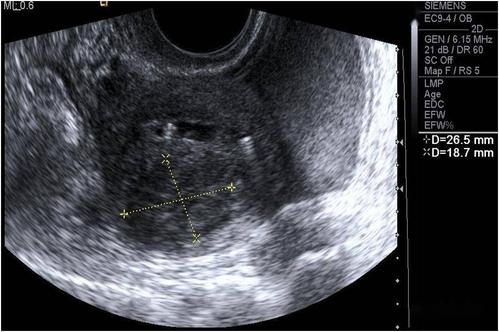

超声典型病例子宫穿孔

超声典型病例:子宫穿孔

子宫穿孔超声表现图

子宫穿孔超声图片

子宫穿孔彩超下表现